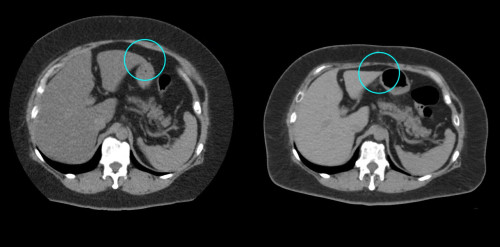

①

50代・女性(ご本人のご厚意で画像提供)

治療内容:チルゼパチド7.5mgの週1回自己注射による脂肪減少と脂肪肝改善

治療期間: 12ヶ月(52週)((用量は2.5mgから開始し最大で15mg。減量効果が得られる必要用量には個人差があります。))

2:脂肪肝の改善

沈着した脂肪の減少による肝臓の平均CT値の増加(20から50へ)(脾臓の平均CT値は両者とも50)

bluntness of the liver edgeの改善(青色部分)